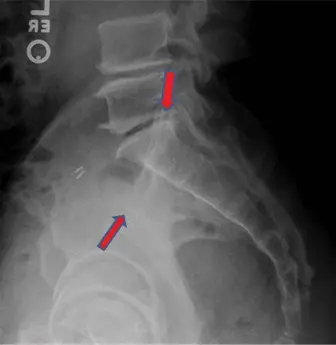

- صورة الحوض الأمامية الخلفية (AP Pelvis): تُظهر تباعد الارتفاق العاني وأي تغييرات في بنية الحوض العامة.

- صورة المدخل (Inlet View): تُظهر الإزاحة الأمامية الخلفية ودوران نصف الحوض، وهي حاسمة لتقييم توسع الارتفاق العاني والمفصل العجزي الحرقفي الأمامي.

- صورة المخرج (Outlet View): تُظهر الإزاحة العمودية لنصف الحوض وتشريح العجز. في إصابات APC II، يجب أن تكون هذه الصورة طبيعية نسبياً، مما يؤكد الاستقرار العمودي.